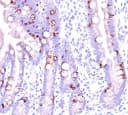

This antibody recognizes a single glycoprotein of 520kDa, identified as MUC2 (Mucin-2). The MUC2 antibody shows no cross-reaction with human milk fat globule membranes, MUC1, or MUC3. Mucins are high molecular weight glycoproteins, which constitute the major component of the mucus layer that protects the gastric epithelium. MUC2 is specifically expressed in goblet cells of the small intestine and colon; in about 65% of colonic carcinomas and about 40% of gastric carcinomas. MUC2 is rarely expressed outside of the GI tract with the exceptions of mucinous carcinoma of breast and clear cell-type carcinomas of the ovary.Host:

IHC-PFormat: